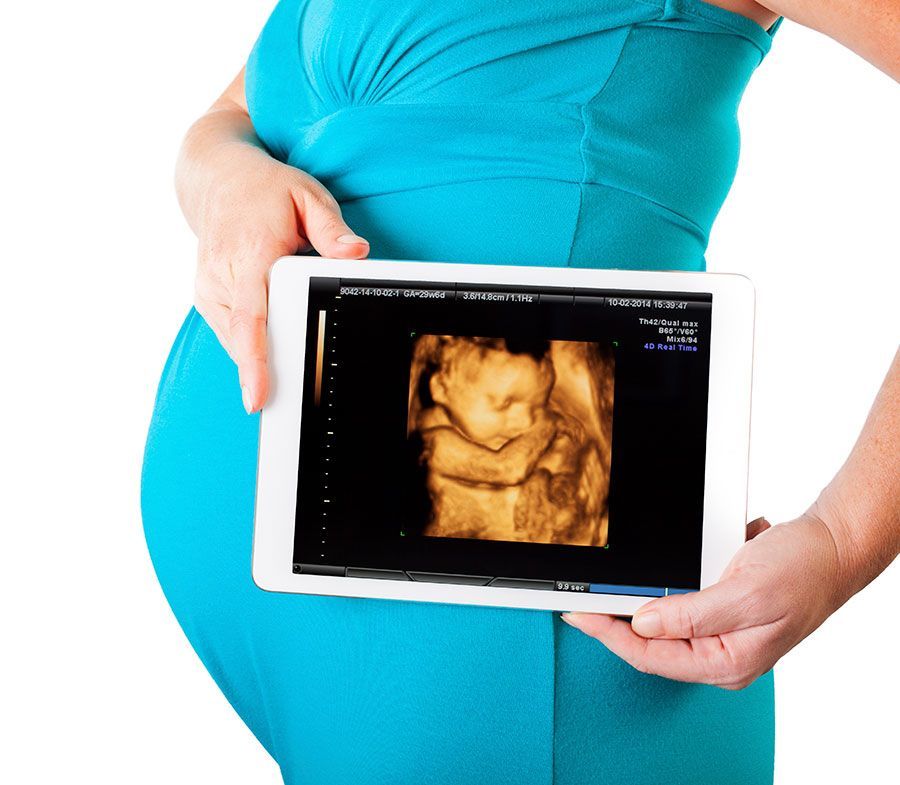

En Ultrasonido Diagnóstico de Hidalgo le brindamos una consulta profesional, realizando Ultrasonido de Embarazo desde su diagnóstico, acompañándole en el crecimiento y desarrollo de su bebe en cada semana de gestación, así como la revisión de los marcadores ultrasonográficos para la detección de alteraciones cromosómicas y estructura del feto. En el primero y Tercer trimestre del embarazo se realiza la revisión de las arterias uterinas para la prevención de la hipertensión de la mujer embarazada.

- Sexo del bebe y grabación del bebe